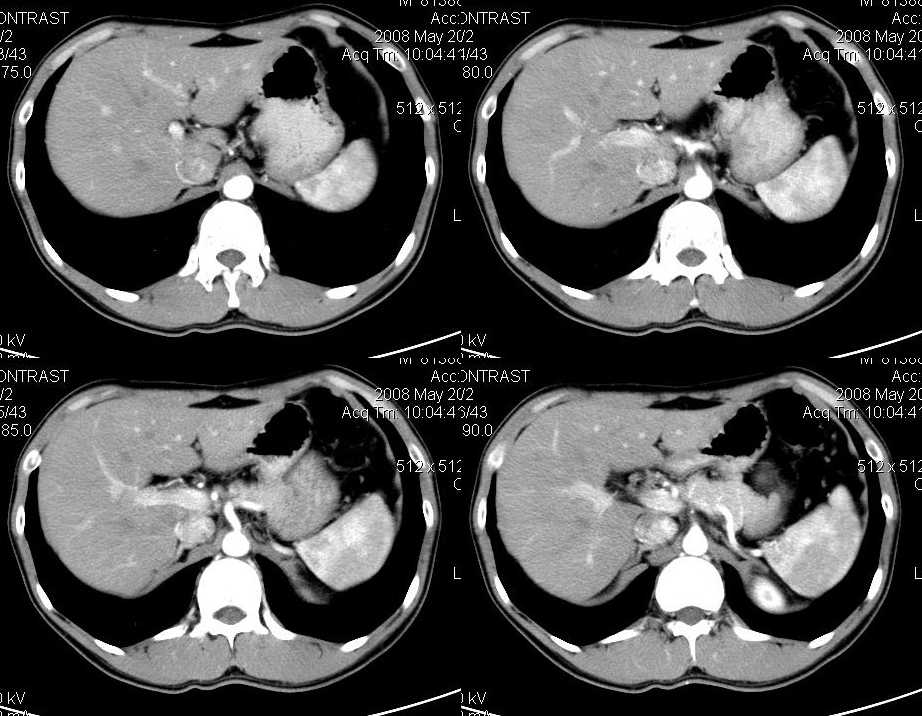

以下是引用liuyue在2008-6-7 15:28:00的发言:[br]典型的:肾癌。[br]动脉期强化明显,而静脉期密度明显降低,呈低密度。